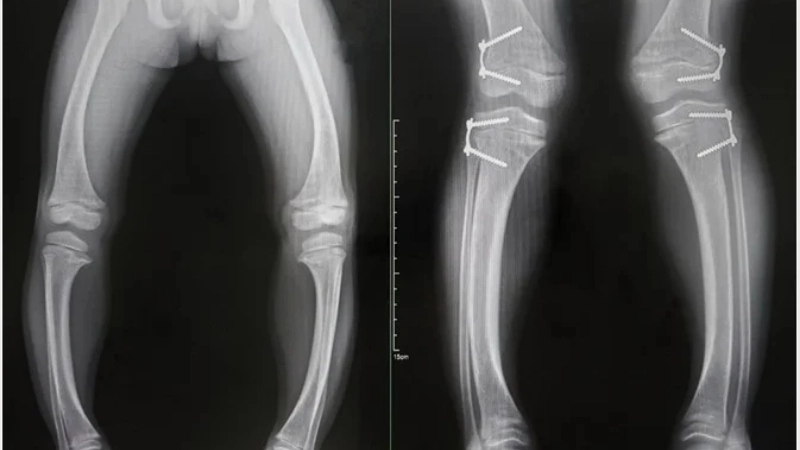

Hình ảnh X-quang biến dạng xương do còi xương